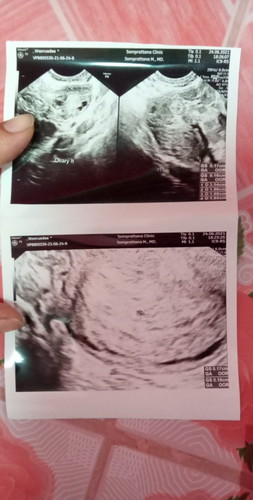

ในใบซาวถุงตั้งครรภ์หนูเล็กมากๆเลยคะ กลัวท้องลมมากกังวลไปหมดเลย...มีใครถุงเล็กมากขนาดนี้ไหมคะซาวตอน5w

ของเราก็เล็กแบบนี้ อีก1 สัปดาห์หมอนัดไปซาวใหม่..เห็นใหญ่ขึ้นมาเยอะเลยคะ แต่ยังไม่เจอตัวน้องนะคะหมอบอกว่าน่าจะประมาณ 6 สัปดาห์ แต่เห็นหัวใจแล้วนะคะพออีก2อาทิตย์ไปใหม่ทีนี้เจอตัวน้องเลยคะ ไม่ต้องเครียดนะคะคุณแม่ ช่วงนี้ดูแลตัวเองดีๆคะ เด่วก็เจอคะ 😉 ะ

ตอน5วีค ถุงเราแค่3มิลค่ะ พอ6วีคขึ้นมา1ซม. ยังไม่เจอเด็กเลยค่ะ มาเจอตอน7วีคค่ะ ที่ถุงเล็ก เพราะไข่ตกช้า ระยะที่นับวัน ไม่ตรงกับขนาดจริงค่ะ

คุณหมอไม่ได้ขยายหรือเปล่าคะ ถุงตั้งครรภ์ต้องเล็กอยู่แล้วค่ะเพราะน้องตัวเล็กมากเท่าเม็ดถั่ว

อายุครรภ์อาจจะยังน้อย รออีกสัก2-3สัปดาห์ ลองไปตรวจดูใหม่ค่ะ

อายุครรภ์ยังน้อยอยู่เลยค่ะ ไม่ต้องกังวลนะคะ